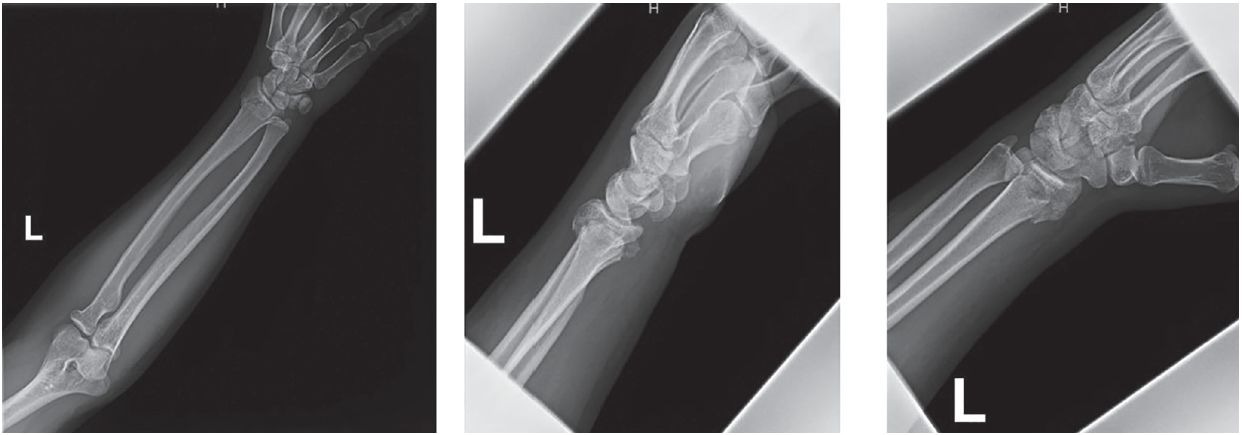

Standard 3-view radiographs were obtained, which demonstrated a left dorsally displaced extraarticular fracture of the distal radius (Figure 1). A reduction under traction and hematoma block was performed to obtain acceptable alignment of the distal radius fracture. The patient’s neurovascular examination remained unchanged throughout the procedure, as well as immediately and 2 hours after reduction. Persistent ulnar palsy, including considerable weakness in the intrinsic muscles of the digits, remained present on the left.